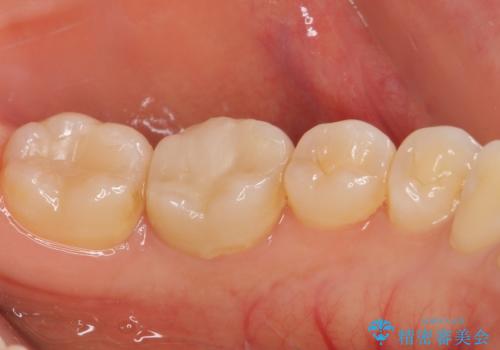

- 近医にてセラミックを装着した左下の奥歯に痛みが続いたとのことで来院された患者様です。

診査の結果、既に歯の神経は失活していたおり、排膿路が認められ、叩いたり触ったりしたときの痛みも確認されました。

根管治療を行った後にオールセラミッククラウンにて補綴することとしました。

初回の治療後には歯肉に認められた排膿の出口などの症状は消えていました。

補綴後6ヶ月経過しレントゲンを撮影したところ、遠心の歯根付近の病変が消失していることが確認できました。